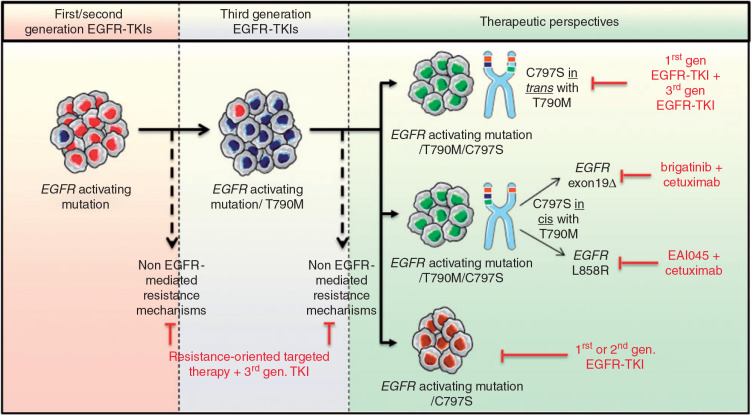

EGFR | p.L858R,p.L861Q,p.T790M,p.C797S,c.exon 19 deletions,c.exon 20 insertions,EGFR 扩增 | 吉非替尼/厄洛替尼/阿法替尼/埃克替尼/达克替尼/奥希替尼/阿美替尼/伏美替尼/帕尼单抗/西妥昔单抗/尼妥珠单抗/Amivantamab/Mobocertinib |

1.EGFR(表皮生长因子受体),约10%的非小细胞肺癌患者中,EGFR基因会发生异常或突变。EGFR突变可能影响肿瘤对特定药物的敏感性。(可参肺癌11基因检测)